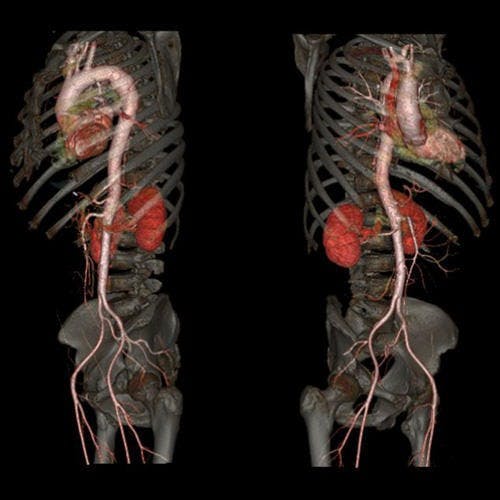

自從X光發明之後,X光電腦斷層掃描一直以來在醫學上都是重要的應用,尤其是檢查腦血管、心血管以及腫瘤篩檢等方面。不過在影像清晰方面仍然有些麻煩,只要患者有一些小小的震動,影像就會模糊。不過若是使用這次GE所發表的革命性電腦斷層掃描,醫生能夠拍下一個完整影像清晰的心臟。

自從X光發明之後,X光電腦斷層掃描一直以來在醫學上都是重要的應用,尤其是檢查腦血管、心血管以及腫瘤篩檢等方面。不過在影像清晰方面仍然有些麻煩,只要患者有一些小小的震動,影像就會模糊。不過若是使用這次GE所發表的革命性電腦斷層掃描,醫生能夠拍下一個完整影像清晰的心臟。